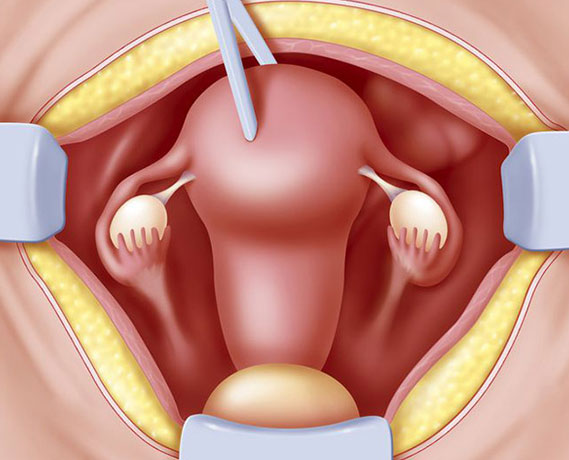

Myomların klinik bulguları genellikle lokalizasyonları ile ilişkilidir. Rahim kavitesinin içine doğru büyüyen submüköz myomlar, uzamış ve ağır kanamaya neden olurlar. Bu myomlar aynı zamanda gebe kalmak isteyen kadınlarda da problem yaratırlar. Subseröz myomlar ise rahimin dış kısmına doğru büyüyen myomlardır. Bazen mesaneye bası yaparak idrar ile ilgili şikayetlere neden olabilirler. Eğer rahmin arka tarafına doğru büyürlerse rektuma bası ile kabızlık, spinal sinirlere bası ile bel ağrısına neden olabilirler.

Myomlar, genellikle gebe kalmaya engel olmasalar bile yerleşim yerlerine bağlı olarak spermlerin rahim içine girişlerine ya da tüplerden geçişine engel olabilirler. Yine rahim iç tabakasına yerleşmiş olan myomlar embriyo gelişimini engelleyebilirler. Gebelikte ise myomlar sıklıkla karın ve kasık ağrısı şikayetine neden olurlar. Bazı nadir durumlarda ise düşük ya da erken doğuma sebebiyet verebilirler.

Myomlar, genellikle tedavi gerektirmezler fakat hastada aşırı kanama, anemi, ağrı ya da gebeliğe engel durum oluşturuyorlarsa cerrahi olarak çıkarılmaları gerekir.

- Yumurtalık Kisti Ameliyatı

- Rahim Ameliyatı

- Miyom Ameliyatı